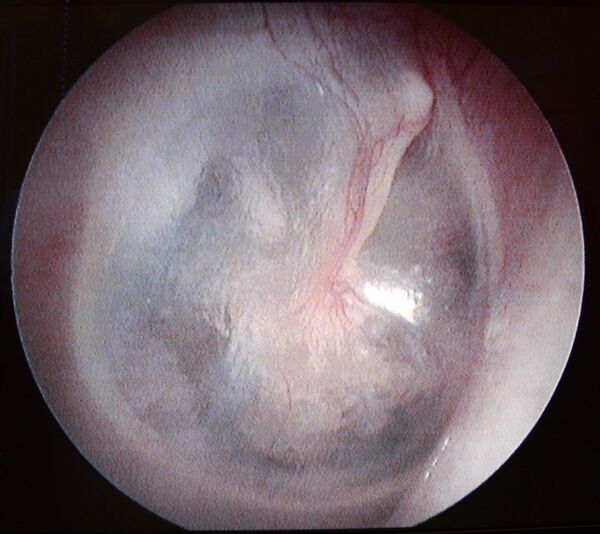

Мирингопластика

Мирингопластика (новолат. myringoplasty) — операция по восстановлению целостности барабанной перепонки.[2]

Метод мирингопластики, позволяющий достичь необходимой герметичности и избежать последующих дегенеративных изменений в трансплантате. Для устранения перфорации, из фасции височной мышцы формируют двойной фасциальный лоскут, размещают его с двух сторон барабанной перепонки.[3]